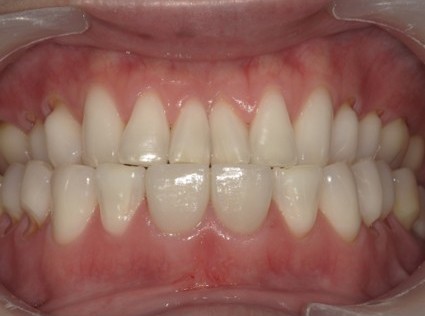

| 主訴 | 膿で腫れて痛みが強い、他の歯医者で抜歯しかないと言われ相談で来院 |

| 状態 | 自発痛もかなり強く、写真のように膿が溜まって腫れ上がっている状態 |

| 治療内容 | X写真から根先部の根先病変が原因と思われるため、根管治療を行った。 骨成長因子を用いて、骨の再生を促した。 結果、2年経過後病変の大きさが1/3まで縮小し、骨の再生が認められる。 本人も症状や違和感がなくなったため、一時的に補綴物をセラミックで行った。 |

| 料金 | 根管治療10万円、ファイバーコア2万円、EーMAX11.5万円 |